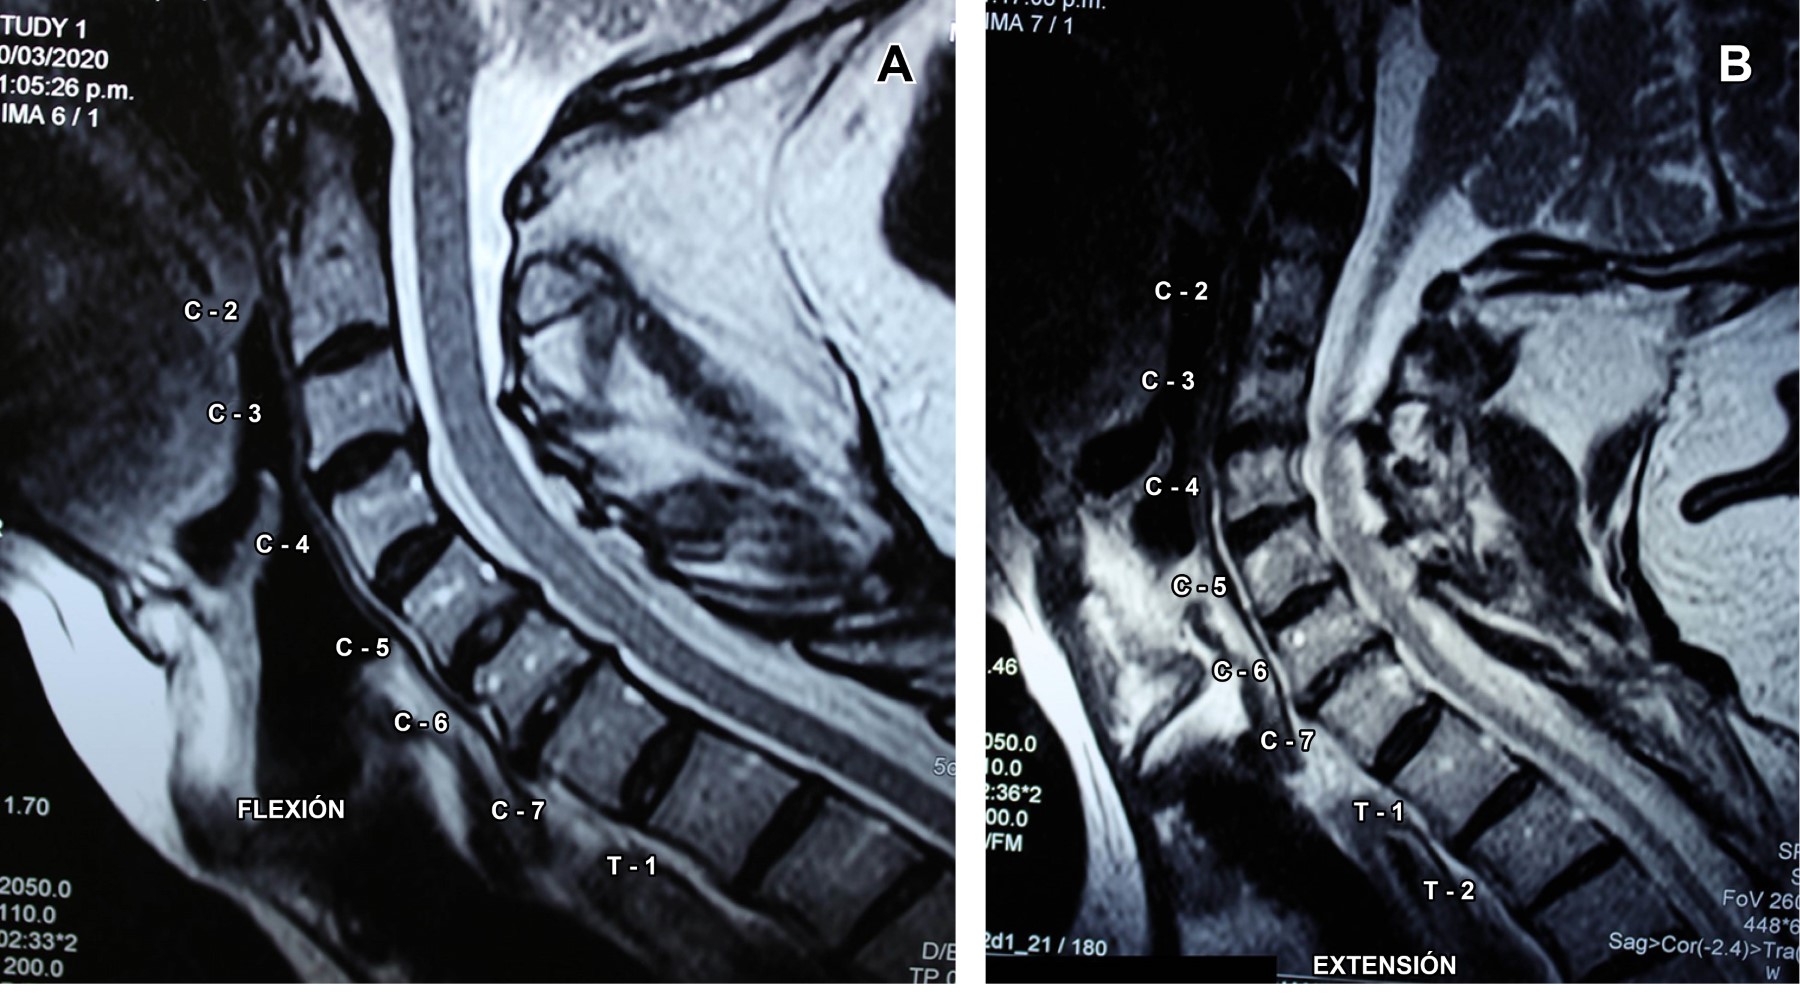

Con los datos clínicos se establece diagnóstico de síndrome de lesión del cordón medular posterior, específicamente del fascículo gracilis, sustentado en pérdida de la sensibilidad propioceptiva, epicrítica y vibratoria por debajo de C7 y marcha atáxica con signo de Romberg positivo y miembros superiores normales, pues se consideró que el plegamiento del ligamento amarillo y de la duramadre pudieran contribuir a la compresión dorsal de la médula espinal en la hiperextensión, causando presión sobre la médula espinal. Por lo que se efectuó resonancia magnética cinética de columna cervical (Figuras 1 y 2), la cual confirmó el diagnóstico, por lo que se le programó para cirugía de columna cervical.

La resonancia magnética cinética (kMRI, por sus siglas en inglés) es una técnica de imagen que combina el excelente contraste de tejidos blandos y la capacidad multiplanar de la resonancia magnética (MRI) convencional con capacidades "funcionales" o cinemáticas, ya que permite que los pacientes sean examinados en múltiples posiciones. Se han utilizado diversas técnicas y dispositivos de posicionamiento para obtener estas imágenes de pacientes en posiciones de carga y carga de peso, en posición vertical y reclinada, y particularmente en flexión, neutra, extensión y rotación axial, las cuales demuestran la movilidad y la cinemática in situ que pueden no ser evidentes con la resonancia magnética estática convencional.1

En cuanto a los cambios dinámicos del ligamento amarillo, en el estudio de Sayit y colaboradores,2 en el cual utilizaron kMRI en 257 pacientes, se observó que a medida que la columna cervical se mueve en flexión-extensión, el grosor del ligamento amarillo es significativamente mayor en extensión, en comparación con la flexión en los niveles C3-4, C4-5, C5-6 y C6-7, sin diferencias en los niveles C2-3 o C7-T1. Por lo que se concluye que kMRI puede demostrar hallazgos que no son evidentes en la resonancia magnética convencional y puede ser de gran utilidad en un entorno clínico cuando las técnicas convencionales de diagnóstico por imagen y diagnóstico no logran identificar la fuente de la patología cervical de un paciente.3

Figura 2